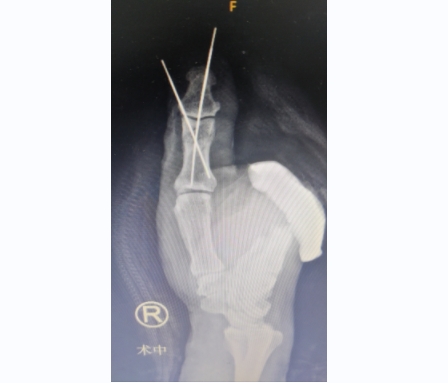

术中处理